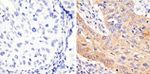

Phospho-STAT3 (Tyr705) Antibody in Immunohistochemistry (Paraffin) (IHC (P))

Phospho-STAT3 (Tyr705) Antibody (710093) in IHC (P)

Immunohistochemistry analysis of STAT3 (pY705) showing staining in the cytoplasm of paraffin-embedded human cervical carcinoma (right) compared to a negative control without primary antibody (left). To expose target proteins, antigen retrieval was performed using 10mM sodium citrate (pH 6.0), microwaved for 8-15 min. Following antigen retrieval, tissues were blocked in 3% H2O2-methanol for 15 min at room te... View More {{ $ctrl.currentElement.advancedVerification.fullName }} 验证信息 View more